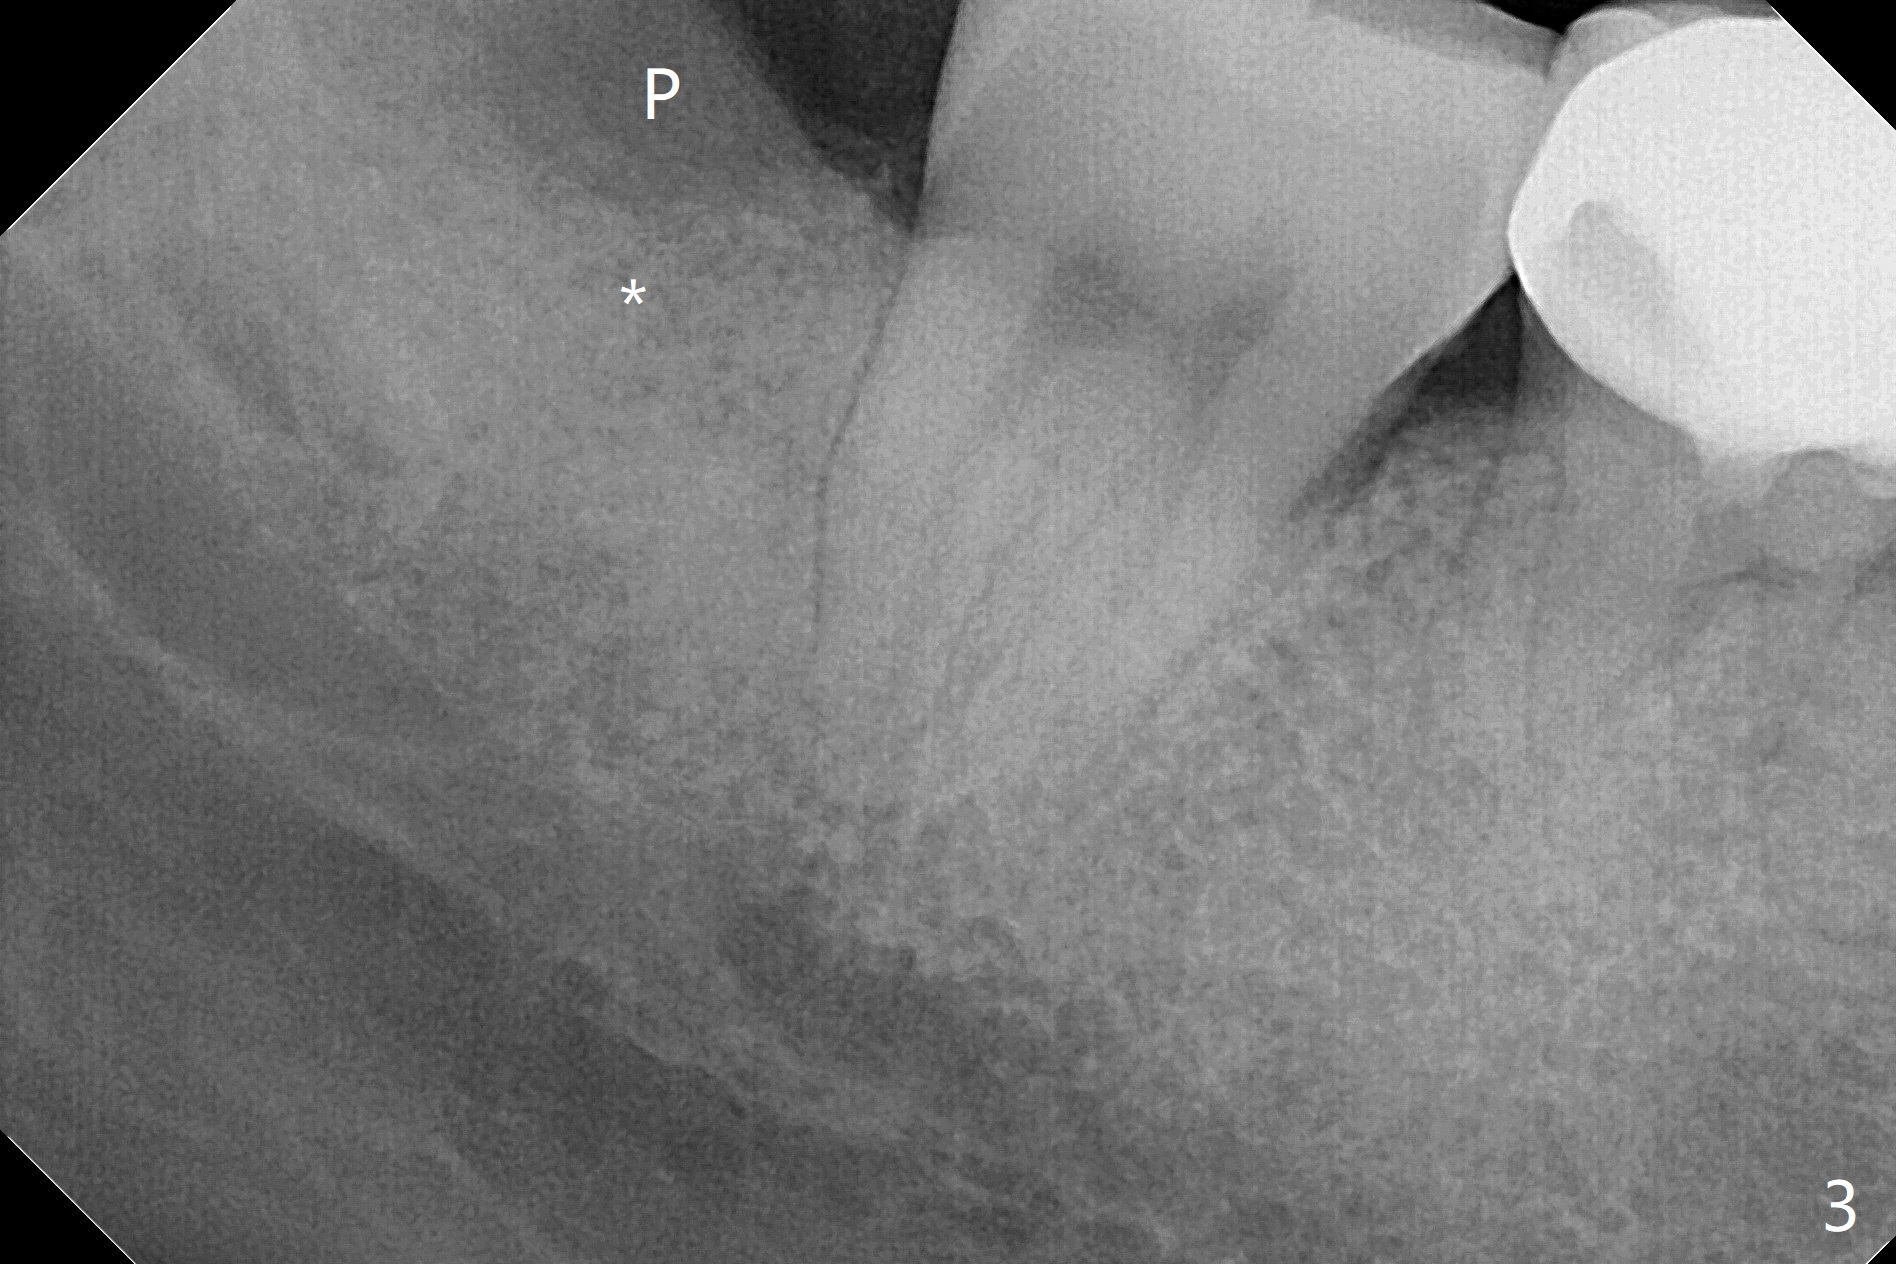

A 37-year-old woman requests extraction of the tooth #32 (Fig.1,2 (< cheek bite)). Note no bone between the last 2 molars. The tooth is extracted with incision, but without bone removal. Vanilla graft (Fig.3 *) is placed as mesial as possible, while Osteogen plug (P) coronal before suturing. The white dashed line in Fig.4 most likely represents the mesial wall of the 3rd molar socket (fused roots). The distal root of the 2nd molar seems to be partially covered by the bone.